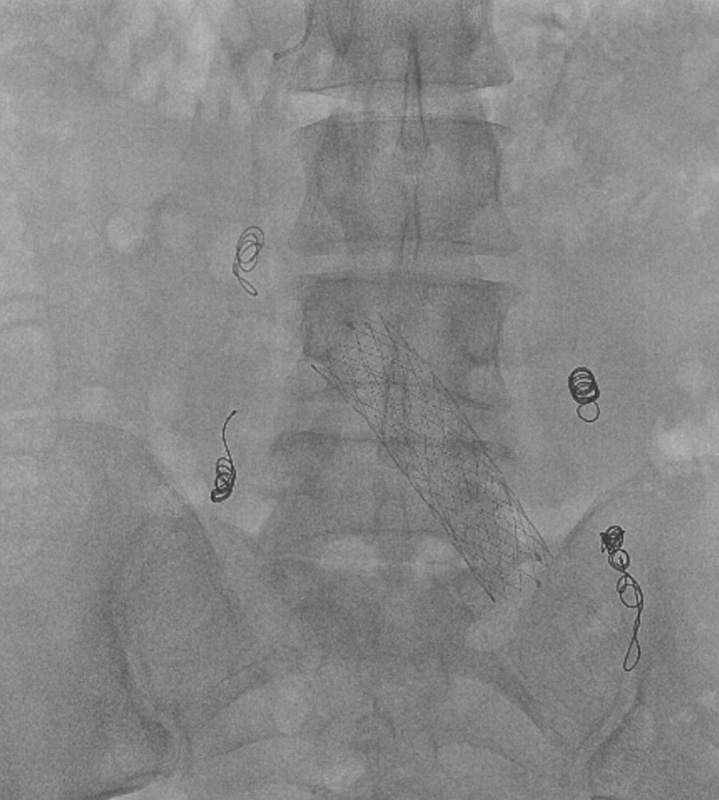

Примером лечения варикозной болезни малого таза в АО ЦЭЛТ может служить история болезни молодой женщины из Дагестана, которая обратилась к нам по поводу хронической тазовой боли. Она беспокоит ее уже несколько лет и существенно мешает жить. Длительное время пациентка лечилась у разных специалистов и уже перенесла стентирование левой подвздошной вены. Несмотря на проводимую терапию и хирургическое вмешательство, жалобы не проходили. После онлайн-консультации в сосудистом центре АО ЦЭЛТ, пациентка прилетела к нам для флебографии и эмболизации варикозно расширенных вен малого таза. Через прокол в вену предплечья мы установили специальный порт – интродьюсер – для проведения медицинских инструментов в сосудистое русло. Специальный изогнутый катетер по проводнику был заведен в правую и левую варикозно расширенные яичковые вены. Каждая вена была с признаками несостоятельности клапанов, а диаметр их превышал 12 мм (при норме 4-6). Поэтому, мы выполнили женщине дистально-проксимальную эмболизацию яичниковых вен кубитальным доступом. Операция была настолько малотравматична, что уже утром следующего дня больная смогла улететь домой.

На фотографиях видно, как варикозные вены сначала заполняются контрастным веществом, имитирующим кровь. После установки спиралей, такого контрастирования не отмечается.